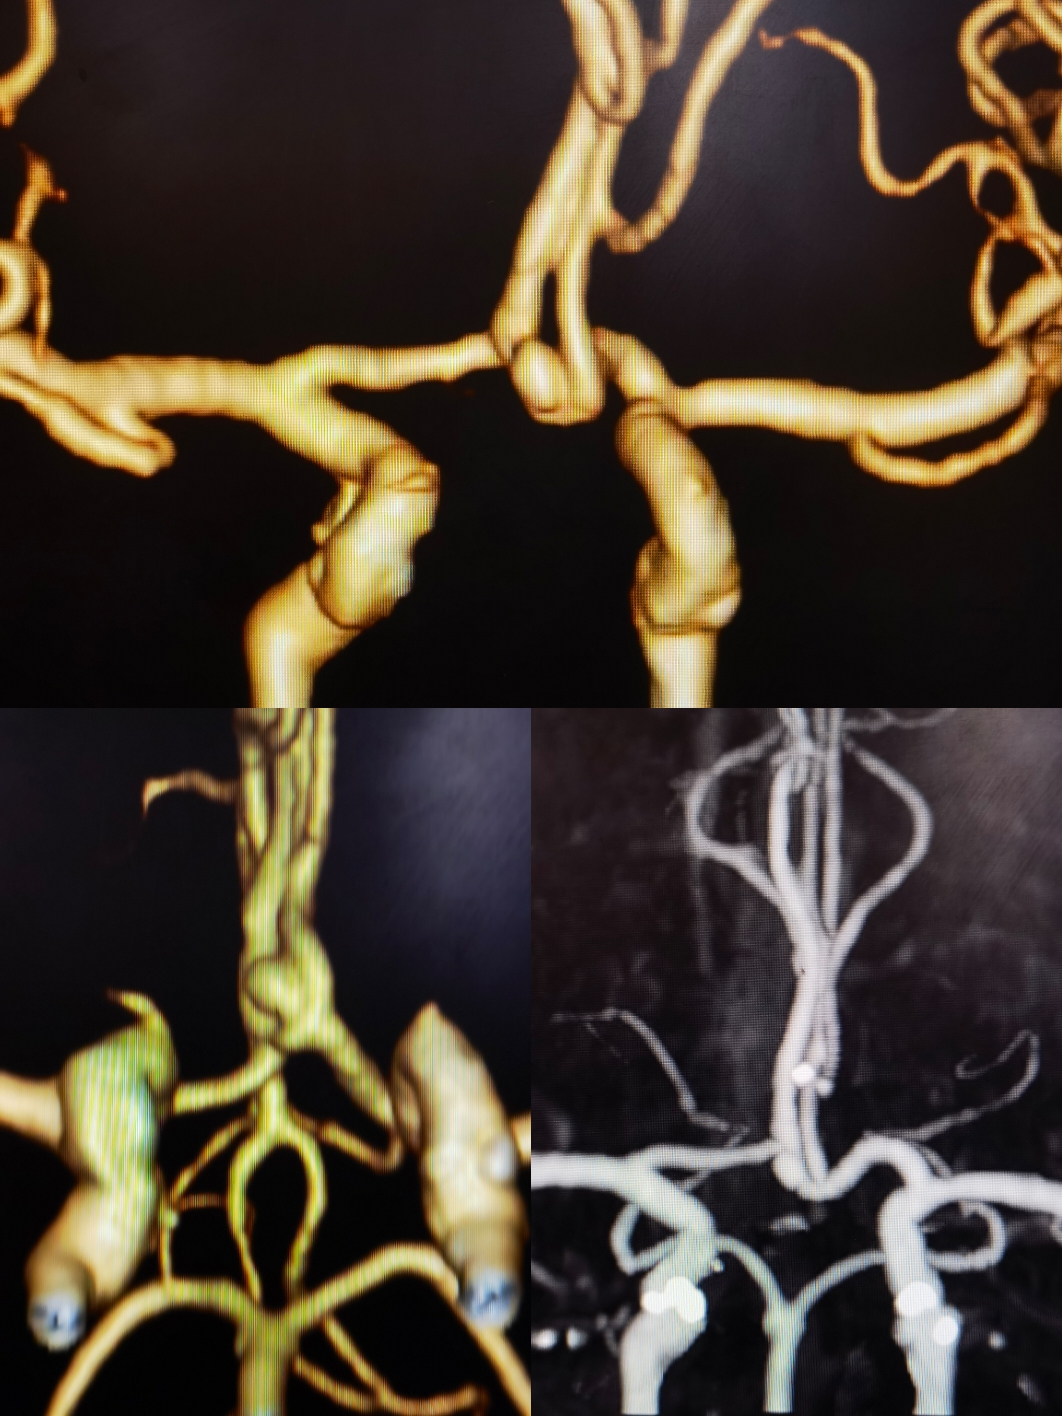

主动脉弓1型弓,右侧颈内:右侧大脑前A1存在

双椎造影无特殊

左侧颈内造影:前交通动脉瘤,窄颈

3D重建情况